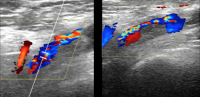

Ultrasound pictures of a thrombosis in the right iliac vein, extending to the right common femoral vein in a patient with COVID-19. Image courtesy of Behnood Bikdeli.